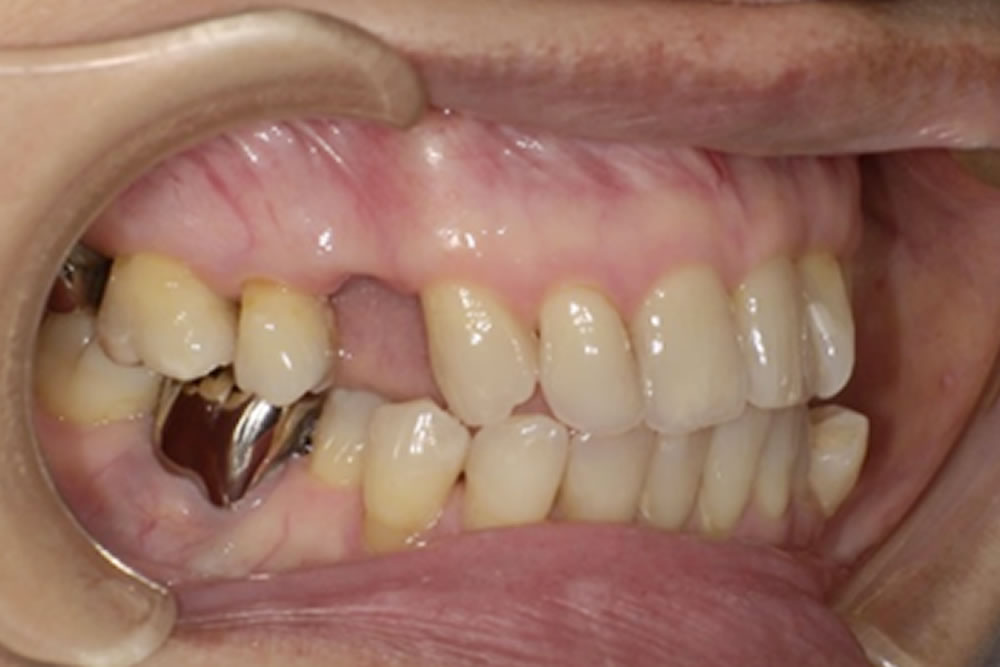

ミラクルデンチャー症例123(60代 女性)

こちらの方は、当院が運営する「入れ歯相談サイト」をご覧になり、無料相談を通じて来院されました。右上の欠損部分をどの治療法で補うべきか検討されており、インプラント・ブリッジ・入れ歯の3種類の治療法について、それぞれの特徴やメリット・デメリットを知りたいというご希望がありました。